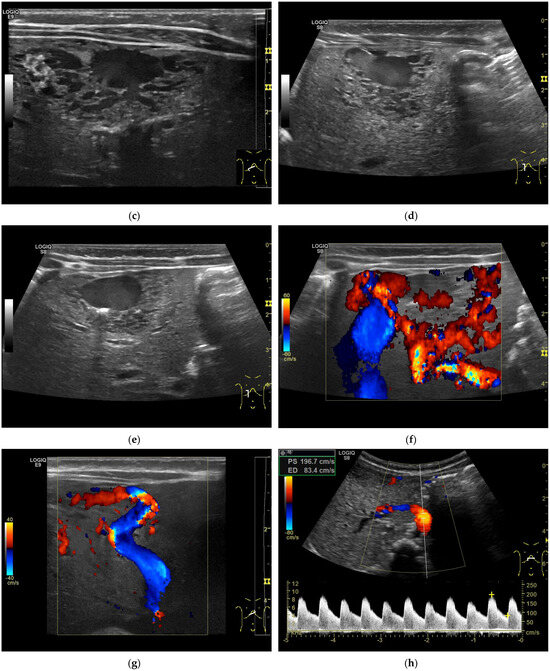

CEUS: HAS is characterized predominantly by nodular peripheral enhancement during the arterial phase and portal venous phase, while diffuse chaotic or reticular enhancement could also be seen. In the late phase, HAS typically shows hypoenhancement, possibly with partial rim-like enhancement or isoenhancement, without centripetal filling [10]. In contrast, typical hemangiomas could be accurately diagnosed by CEUS with peripheral nodular enhancement and centripetal filling, which should be differentiated from HAS (Figure 4).

Figure 4.

A 17-year-old female with a focal liver lesion in the right liver lobe and a small oval cyst in the surrounding area (a). Arterial phase hyperenhancement predominantly in the periphery with a rim and septae-like structures with non-enhancing areas (b) and washout are documented (c). Needle biopsy with histological evaluation revealed angiosarcoma of the liver.